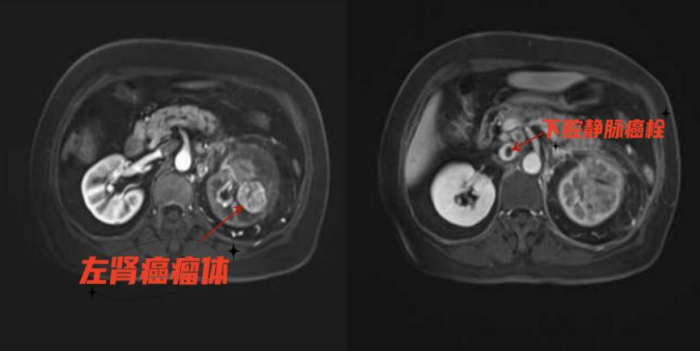

66岁女患,因左侧腰部反复疼痛1月,于外院行泌尿系CTU和上腹部MRI后考虑左肾癌合并腔静脉癌栓,为求进一步诊治就诊于贵州茅台医院泌尿外科。在对患者病情进行充分评估后,决定为患者行“左肾癌根治术+腔静脉癌栓取出术”,切除肾肿瘤和取出腔静脉内癌栓,改善患者预后。

“肾癌根治术+腔静脉癌栓取出术”被称之为“皇冠上的明珠”,是泌尿外科公认的最复杂、难度最大、风险最高的手术,因解剖部位的不同,左肾癌合并下腔静脉癌栓比右侧手术难度更大。